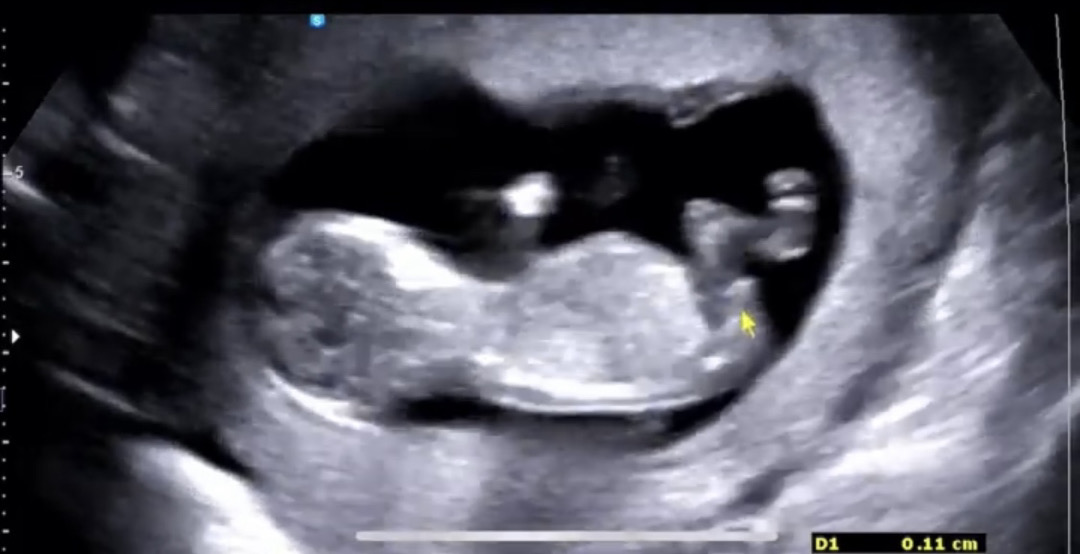

12주 0일차 각도법 투표해주세용🙏🏻🩵

사진이 하나밖에 안올라가네요ㅠㅠ 지피티는 딸이라하고 빌리ai는 사진에따라 아들딸 나뉘네요ㅠㅠ 의견부탁드려용🤍